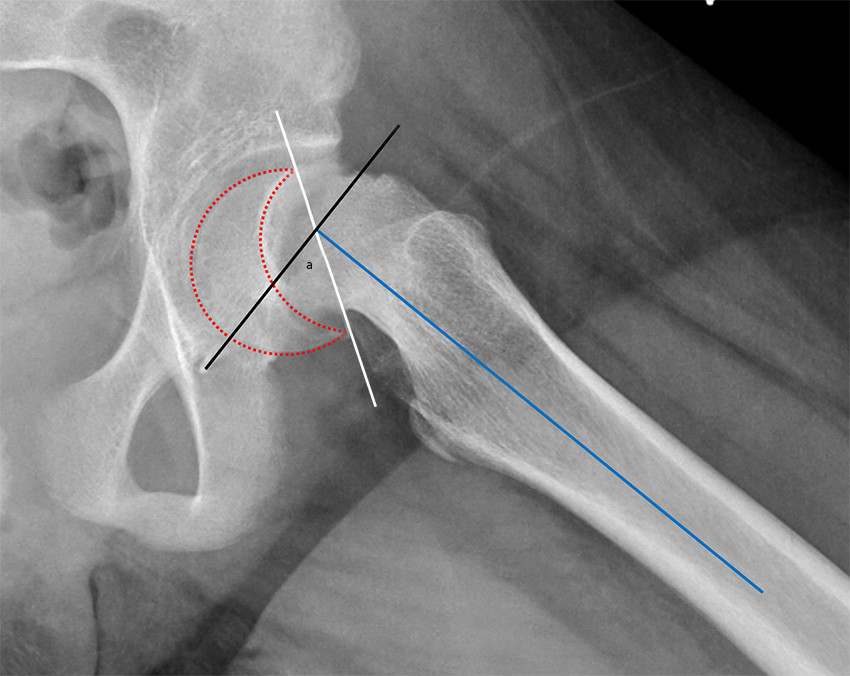

Dagens kliniske klassifikasjon skiller mellom stabil og ustabil epifysiolysis capitis femoris. Hvis pasienten klarer å vektbelaste med eller uten krykker, klassifiseres glidningen som stabil, og hvis pasienten ikke klarer å vektbelaste, er det en ustabil glidning (8). Radiologisk måles graden av glidning på sidebilde (figur 4). Glidning på < 30° klassifiseres som lett, 30–50° som moderat og > 50° som betydelig.